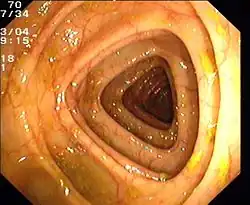

Zur endoskopischen Untersuchung stehen verschiedene Verfahren zur Verfügung. Das Rektoskop ist ein starres Endoskop, das nur zur Beurteilung von Analkanal und Rektum geeignet ist. Eine Sigmoidoskopie zur Beurteilung des Darms bis zum Colon sigmoideum kann mit einem bis zu 60 cm langen, flexiblen Endoskop erfolgen.[54] Die Koloskopie (Darmspiegelung) ist die endoskopische Untersuchung des gesamten Dickdarms mit einem langen Endoskop. Sie gilt als Goldstandard für die Beurteilung der Schleimhaut. Mit diesem Verfahren können nicht nur sichtbare Veränderungen beschrieben, sondern auch Proben entnommen (biopsiert) und kleine therapeutische Eingriffe durchgeführt werden (beispielsweise die Entfernung eines Polypen).[55]